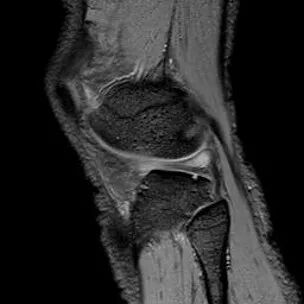

桶柄状撕裂MRI表现

1、宽度减小,在通过半月板体部的冠状面上蝶形消失,同时可见内移的半月板位于髁间窝、交叉韧带旁2、矢状面示残余的前角或后角变小或截断3、半月板前(后)角增宽或双半月板前(后)角征4、双前交叉韧带或双后交叉韧带征

桶柄状撕裂:宽度减小,在通过半月板体部的冠状面上蝶形消失,同时可见内移的半月板位于髁间窝、交叉韧带旁